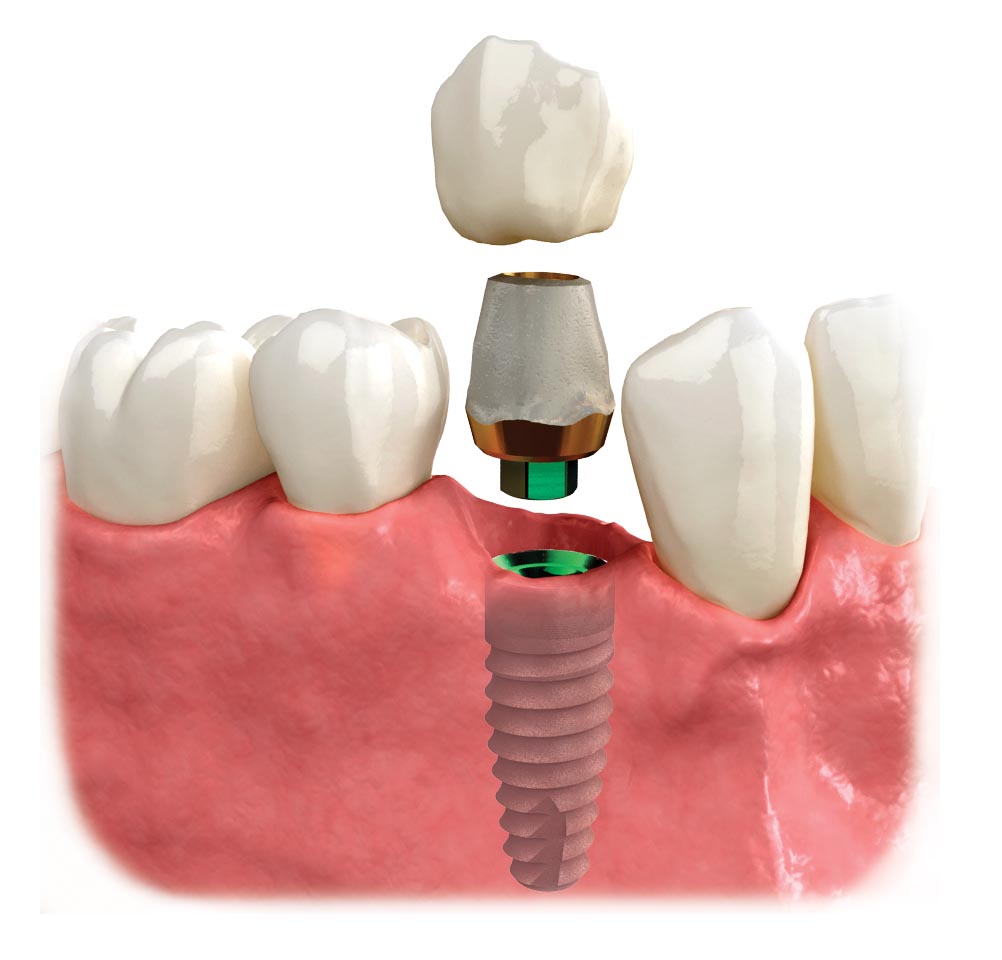

What is a Dental Implant? | DDi

Dental Implant, Single Tooth

Astoria Dentist Answers: What is a Dental Implant? | Astoria, NY